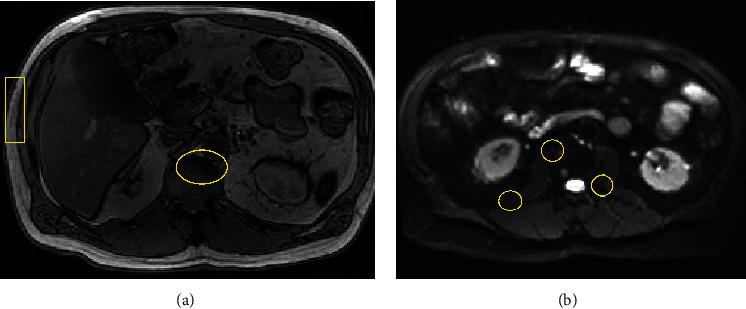

Chronic lymphocytic leukemia (CLL) typically presents as an indolent disease with a benign disposition in most patients. In select patients, CLL can progress into a more aggressive disease via its original morphology, following a Richter transformation to an alternative non-Hodgkin's lymphoma, or with the concomitant development of multiple myeloma. In an extremely rare subset of individuals with CLL, an extramedullary plasmacytoma may coexist. This case report seeks to describe the diagnosis and treatment of a patient with concurrent CLL and a plasmacytoma.

慢性淋巴细胞白血病(CLL)在大多数患者中通常表现为一种惰性疾病,具有良性病程。在部分患者中,CLL可通过其原始形态进展为侵袭性更强的疾病,发生里氏转化成为另一种非霍奇金淋巴瘤,或同时合并多发性骨髓瘤。在CLL患者的一个极其罕见的亚组中,可能并存髓外浆细胞瘤。本病例报告旨在描述一名同时患有CLL和浆细胞瘤患者的诊断和治疗情况。